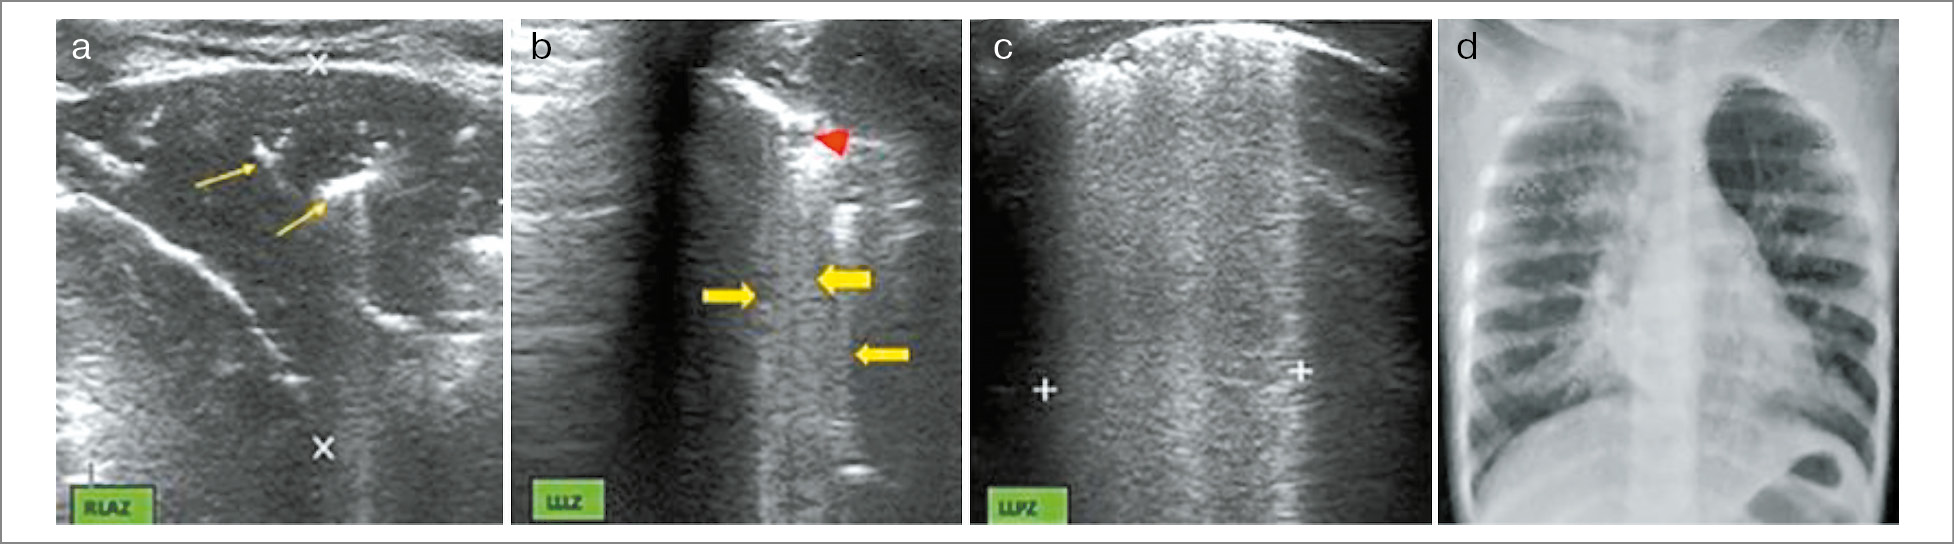

Так, по данным одной из публикаций зарубежных авторов, при анализе 200 пациентов с инфекционным поражением легких участки консолидации (0,5–1 см) обнаружены у 56 (28%) детей с бактериальным поражением легких (рис. 5). Большое количество В-линий и наличие интерстициального синдрома было характерно для вирус-индуцированных поражений легких (у 83 пациентов – 41,5%), а также сочетание зон консолидации и интерстициального синдрома (смешанная картина) замечено на УЗИ легких у 46 (23%) детей с микст-инфекцией (рис. 6) [26].

Рис. 5. Семимесячный мальчик с бактериальной ВП [26].

Рис. 6. Годовалый мальчик с вирусным поражением легких [26]: a – наличие субплеврального гипоэхогенного уплотнения размерами 3,5×2,5 см в правой нижней передней части с линейными/точечными эхогенными очагами (желтые стрелки), представляющими сонографическую воздушную бронхограмму; b и c – признаки интерстициального поражения также включают небольшое округлое субплевральное уплотнение (красная стрелка) и множественные очаговые В-линии (желтые стрелки) в левом нижнем боковом сегменте.

На рис. 6 видны консолидация размерами 2,8×2,3 см с точечной сонографической воздушной бронхограммой (желтые стрелки) и знаком разрыва (красные стрелки) в левом верхнем сегменте и участок консолидации в левом среднем сегменте, что характерно для бактериальной пневмонии. По лабораторным данным отмечались лейкоцитоз до 21×109 и повышенный уровень СРБ. Ребенок получал АБТ и был выписан на 8-е сутки.